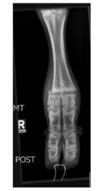

D) Le virus de la diarrhée virale bovine (BVD), en plus de son effet immunosuppresseur, entraîne une réaction inflammatoire de l’appareil respiratoire

Complexe respiratoire bovin

=>BHV-1: Herpesvirus bovin 1 (IBR)= VRS(Hyperhémie muqueuse nasale) atteinte et =>avortemet, oedem corneen